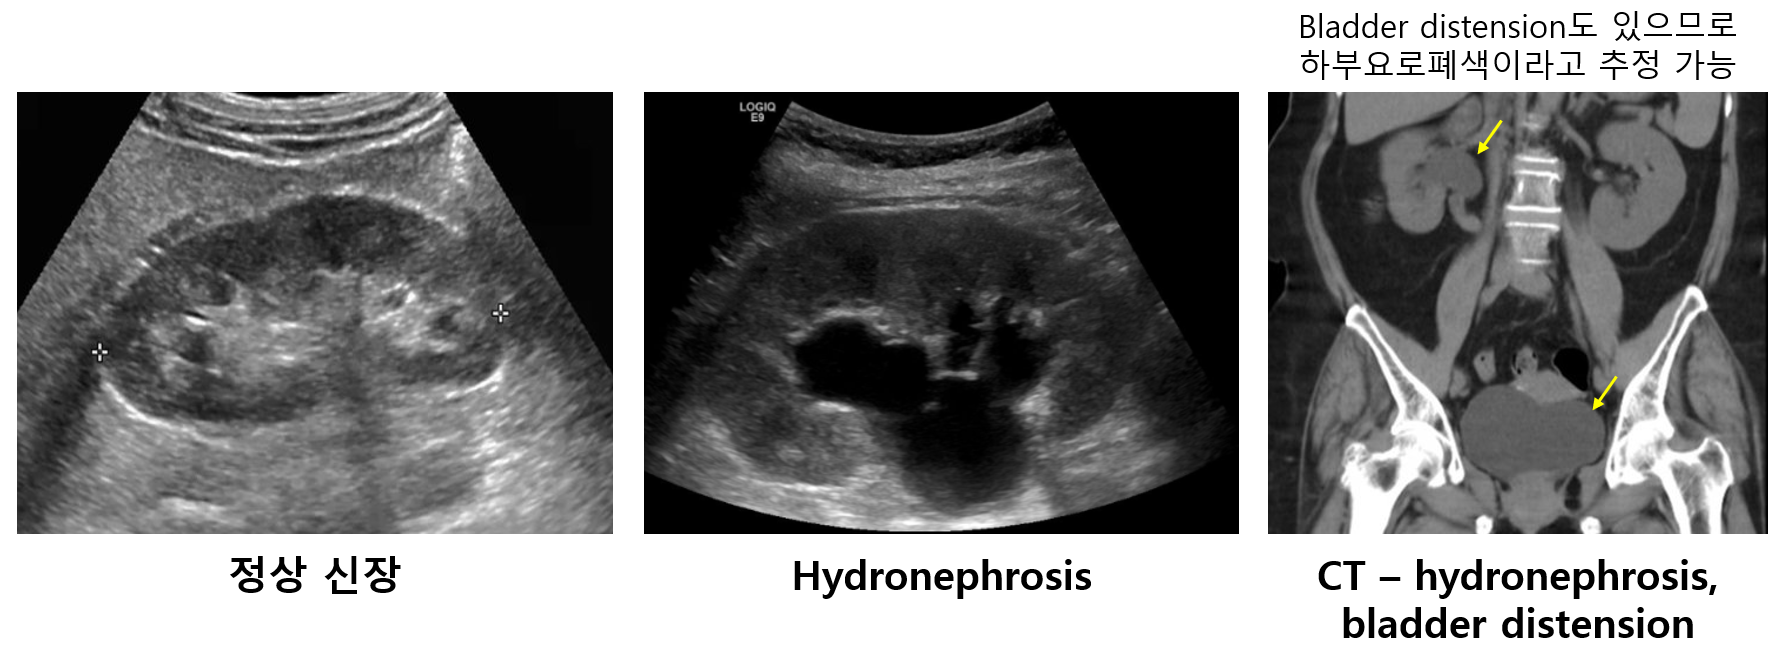

거의 매년 빠지지 않고 출제되는 중요한 파트이다. 하나의 '질환'이 아니라, 여러 다른 질환들에 의해 발생할 수 있는 '임상적 상태'라는 것을 잘 이해하고 있어야 한다. Prerenal/renal/postrenal AKI의 감별진단이 대부분의 문제의 핵심이며, obstruction이 특징적인 postrenal AKI를 먼저 감별한 후, 병력과 lab을 보고 prerenal AKI와 intrinsic AKI를 감별하면 된다. FENa를 직접 계산할 수 있도록 공식을 꼭 숙지하도록 한다. Postrenal AKI 의심 시 가장 먼저 폴리 도뇨관을 삽입하여 소변 배출 여부를 확인하고, 신장 초음파로 hydronephrosis 확인, 복부 CT로 폐색 부위 확인을 진행한다.

1) Postrenal 감별 (요로폐색 단원 참고)

(1) 도뇨관 삽입: 소변 배출시 진단

(2) 신장 초음파: Hydronephrosis 소견시 진단

(3) CT/MRI 등: Hydronephrosis 소견시 진단 + 폐색의 위치 및 원인 파악